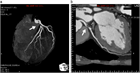

1. 労作性胸痛(ないし安定狭心症)の原因となる冠動脈疾患の診断アルゴリズムが、これまでの運動負荷心電図優位から、検査前確率(PTP)や臨床的尤度(CL)の評価に従った検査選択に代わった。